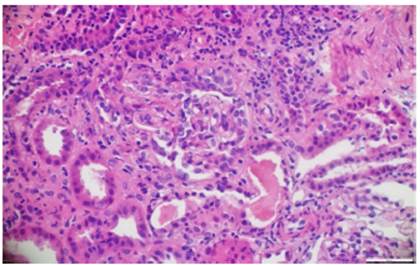

Paraclínicos de ingreso evidenciaron anemia (hemoglobina de 8,9 g/dL), hematuria y proteinuria (75 mg/dL) en muestra espontánea de orina, elevación de azoados (BUN = 45 mg/dL, creatinina sérica = 2,9 mg/dL), complemento sérico C3 y C4 normales, anticuerpos antinucleares y anticuerpos antimembrana basal glomerular negativos, PR3-ANCA negativo < 3,5 U/mL (negativo < 5 U/mL) y MPO-ANCA positivo 72 U/mL (negativo < 5 U/mL). Al ingreso se sospechó glomerulonefritis postestreptocócica complicada versus nefritis lúpica. Ante el aumento progresivo de los azoados y del deterioro clínico de la función renal, se requirió inicio de hemodiálisis y practicar biopsia renal.

La patología renal mostró proliferación crescéntica activa de origen celular, con actividad alta, necrosis fibrinoide extensa, infiltración leucocitaria y evidencia de infiltrado linfoplasmocitario en el intersticio, asociado a 10% con fibrosis. No había evidencia de depósitos de complejos inmunes (figs. 3 y 4).

Figura 3 Hematoxilina y eosina. Extensas semilunas celulares que colapsan el penacho glomerular. 10x.

Figura 4 Hematoxilina y eosina. Semilunas fibrocelulares con obliteración de la luz capilar en el penacho glomerular. 10x.